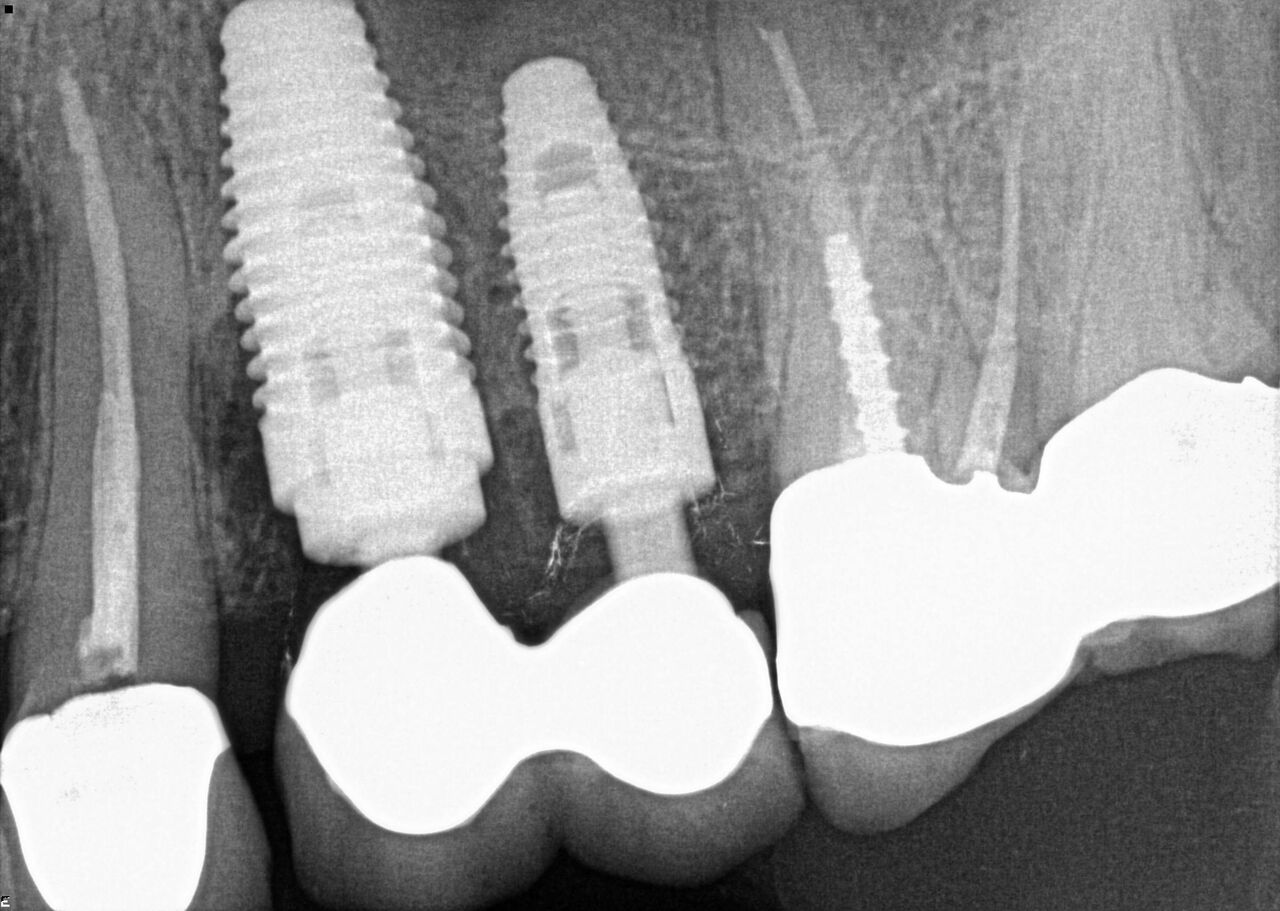

(17.) Case 3 initial radiograph of bridge on Nos. 6 through 9 and crown on No. 10.

Figure 17

(18.) Case 3 initial radiograph of bridge on Nos. 6 through 9 and crown on No. 10.

Figure 18

(20.) 6-month integration confirmation of Nos. 6 through 10.

Figure 20

(21.) 6-month integration confirmation of Nos. 6 through 10.

Figure 21

(24.) Radiograph of postoperative individual crowns on Nos. 6 through 10.

Figure 24

(25.) Radiograph of postoperative individual crowns on Nos. 6 through 10.

Figure 25

A 42-year-old man presented with a very loose bridge on Nos. 6 through 9 with periodontally compromised retainers on Nos. 6 and 9 (Figure 17 through Figure 19), and endodontically involved No. 10 with a calcified canal. Teeth Nos. 6, 9, and 10 were extracted, the sockets fully debrided, and pontic soft tissue on Nos. 7 and 8 sculpted to be symmetrical in soft tissue contour with the contralateral lateral incisor and central incisor locations. Implants were secured in position Nos. 6 through 10 (Figure 20) in excess of 45 Ncm, the bone was milled to provide unimpeded seating of temporary abutments, and temporary crowns were fabricated chairside and adjusted to be out of occlusion in centric relation and all excursions. The temporary crowns were cemented after extrusion of excess cement extraorally and the patient was prescribed antibiotics, analgesics, and instructed in postoperative care particular to immediately provisionally restored implants. At 6 months, integration was confirmed (Figure 20 through Figure 23) and after placement of scanning abutments, the implants and soft tissues were scanned. Final crowns were fabricated from the scanned images and were cemented after extrusion of excess cement extraorally (Figure 24 through Figure 26), and oral hygiene procedures were reviewed.